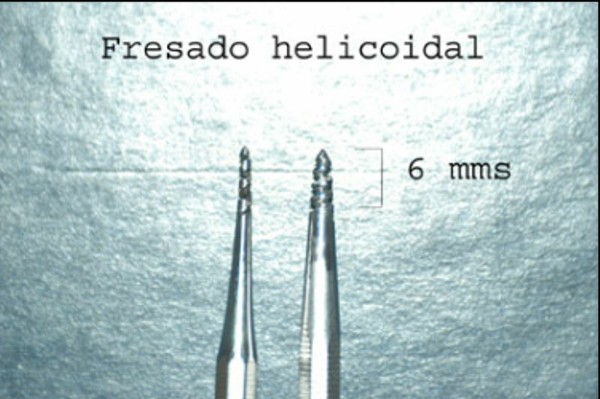

Las extracciones dentarias o EXODONCIAS, son habitualmente realizadas mediante la utilización de instrumentos denominados FÓRCEPS, los que instalados en el cuello de la pieza dentaria a extraer, son movidos de manera oscilante en el eje del diente, lográndose después de un corto período de tiempo, quitar al mismo de la cavidad ósea que lo aloja, en una operación que se denomina LUXACIÓN o AVULSIÓN. FÓRCEPS EN BOCA Esta AVULSIÓN, se produce debido a que el hueso es elástico. Sin embargo , gran parte de las veces esa elasticidad no es suficiente y se parte o rompe la «corteza ósea» que rodea al diente, en su región más cercana a la «zona cortante» del mismo.Esa ruptura o fractura, es favorecida por el uso de los Fórceps, dado que sus «mordientes» se sitúan muy cerca de del hueso. .FÓRCEPS ROMPIENDO LA TABLA TABLA ROTA La idea de crear un instrumento que impida dicha fractura, se basa en la certeza de que cuanto más adentro del diente, y cuanto más cerca de la punta del diente, se efectúe la fuerza de AVULSIÓN, menos posibilidades de fractura existirán por una simple cuestión de física básica: CUANTO MÁS LARGO SEA EL BRAZO DE POTENCIA DE UNA PALANCA, MENOS ACCIÓN TENDRA EL BRAZO DE RESISTENCIA….POR LO TANTO SERÁ NECESARIA MENOS POTENCIA PARA VENCER LA RESISTENCIA… O SEA, CON MOVIMIENTOS MAS DELICADOS , LOGRAREMOS EL MISMO EFECTO. ESQUEMA DE DIENTE MOSTRANDO LA ACCIÓN DE LAS FUERZAS DE UN FÓRCEPS. ESQUEMA DE DIENTE MOSTRANDO LA ACCIÓN DE FUERZAS DE UN AIDA Cuando la especialidad IMPLANTOLOGÍA, no se había desarrollado tal como ahora la conocemos, la fractura de esa «corteza ósea» denominada TABLA EXTERNA O INTERNA del PROCESO ALVEOLAR, carecía de importancia ya que la cicatrización se produce irremediablemente en ausencia de infecciones Sin embargo, a la luz de los conocimientos actuales, la preservación de dichas TABLAS, son de capital importancia para la realización de un IMPLANTE INMEDIATO(Implante colocado en el mismo acto quirúrgico que la extracción), y para el logro de su INTEGRACIÓN Y ESTÉTICA futura. Es por eso que exponemos ante las autoridades competentes, la idea de patentar un instrumento como el que denomino: AVULSIONADOR INTRADENTARIO ATRAUMÁTICO …cuyas características principales son: MATERIAL: ACERO QUIRÚRGICO 316 LONGITUD TOTAL:13 mm PUNTA ACTIVA: 6 mm FORMA DE PUNTA ACTIVA: HELICOIDAL DECRECIENTE DOS GROSORES DE PUNTA. INSTRUMENTO AD HOC Por acción de las espiras , el instrumento se fija en las paredes del canal dentario, produciendo un anclaje que permite la AVULSIÓN. CRESTA ÓSEA COMPLETAMENTE CONSERVADA

DIBUJO TÉCNICO DEL INSTRUMENTO